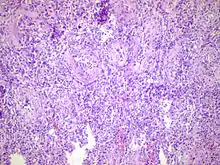

![]() | |

| Acute epididymitis with abundant fibrinopurulent exudate in the tubules. | |